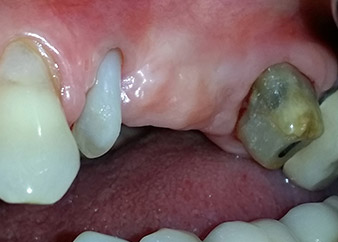

58-годишна пациентка се оплаква от болка и повишена подвижност в нейния мост върху зъб 24 с функция на абатмънт. На лице е периодонтално възпаление с дълбочина на джоба 7 mm мезиобукално и повече от 12 mm дистално, както и включена 3 градусова фуркация. Освен това, рентгенографията показва обширна периодонтална лезия около апикалната зона на (друго място) предварително ендодонтски обработен зъб 24 (Фиг. 1).

Една година по-късно, зъби 25 и 26 са екстрахирани в следствие на травма и поради ендо-перио причини, преди поставянето на моста. Комбинирана ендо-перио лезия е диагностицирана за зъб 24 от неясна етиология. Пациентката иска да задържи нейния мост с абатмънт на зъби 24 и 27 и не приема окончателна, подвижна протеза. По този начин, взаимно решихме да положим всички усилия да запазим и двата зъба, въпреки лошата прогноза за тях, която е базирана на рентгенографски и клинични резултати.

Поставянето на два импланта е планирано на места 25 и 26, в хирургична сесия с отворено периодонтално отстраняване и апикоектомия на зъб 24. В следствие на вертикален дефицит на кост в бъдещото имплантно ложе, планирана е вътрешна аугментация на синус.